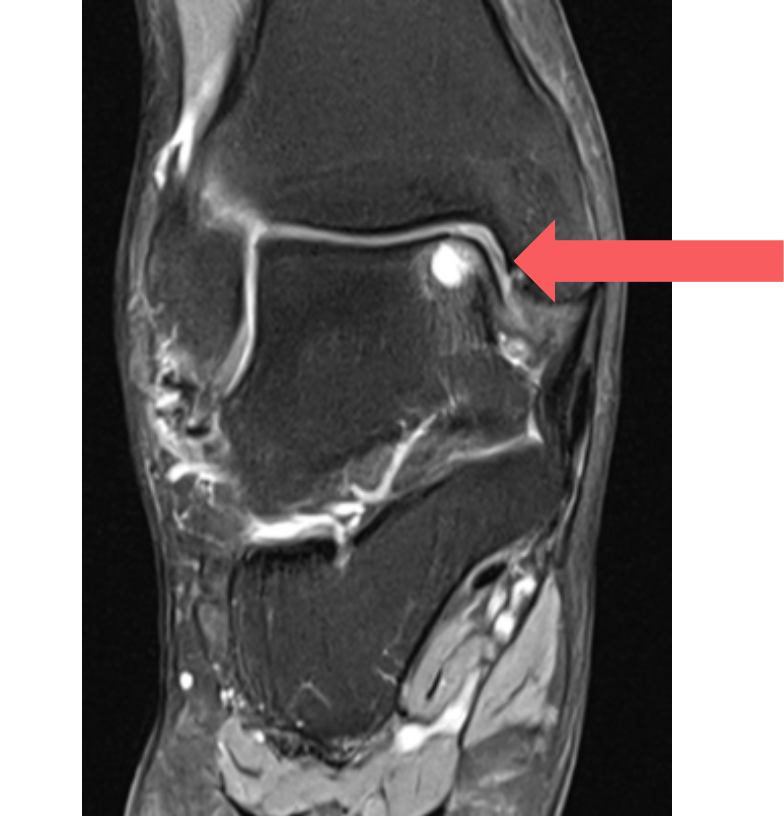

- MRI scan: Best test for detecting cartilage and bone damage, as well as loose fragments.

- CT scan: Provides detailed images of bone defects and helps plan surgery.